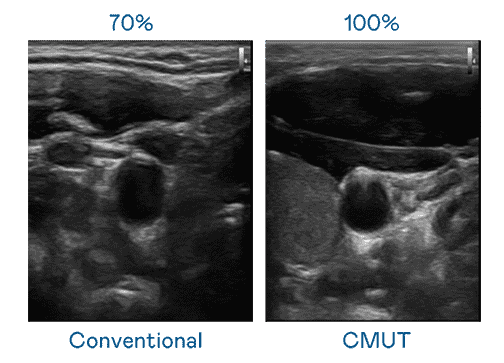

CMUT 技术是一种用电容式微机电元件来产生超音波讯号的技术。。。与传统 PZT 压电式技术相比,,CMUT 频宽增加 30%,,,,更宽频的超音波讯号让影像解析度大幅提升,,,是实现高影像品质医疗超音波扫描、、促进精准医疗发展的关键技术。。。

大频宽带来超清晰影像

超音波影像的解析度高低,,,首先取决于探头能发出的讯号频宽。。。。z6尊龙 CMUT 可提供高清晰的超音波讯号,,提供高频宽、、、、高灵敏度、、、、影像纹理细节更高的超音波影像,,,协助医护人员缩短影像判读时间及利用精准的医疗影像进行诊断。。